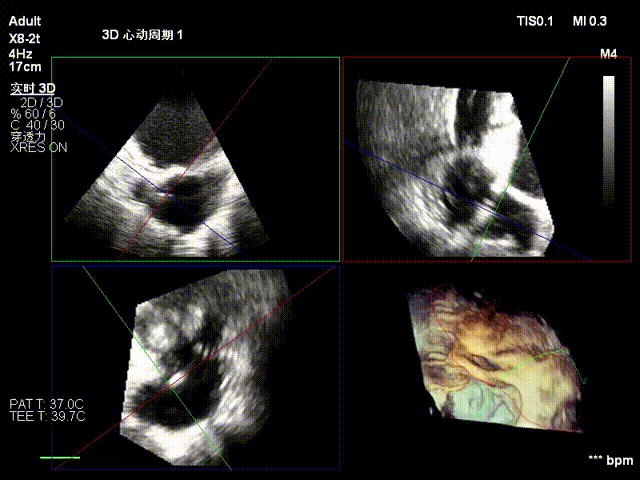

经右颈内静脉穿刺建立通路,置入18Fr鞘管,将K-Clip®输送系统送达右心房。依托三维经食管超声心动图(3D TEE)联合 DSA 双模态引导,经验精准定位瓣环,于后隔交界(P-S commissure)植入14T规格K-Clip®,前后交界(A-P commissure)植入16T规格K-Clip®,实现瓣环多点精准环缩。每枚夹子释放后,团队实时通过超声评估瓣叶对合及反流改善情况,严格遵循 “精准定位 - 锚定验证 - 安全解离” 的规范化操作流程,确认无瓣叶损伤、瓣口狭窄及心包并发症后,完成器械解离与撤出。

3. 控弯旋转输送器指向靶点,3D MPR平面攻入锁定螺丝

4. 调整Oreintation后夹持臂着陆,缓慢关闭夹持臂